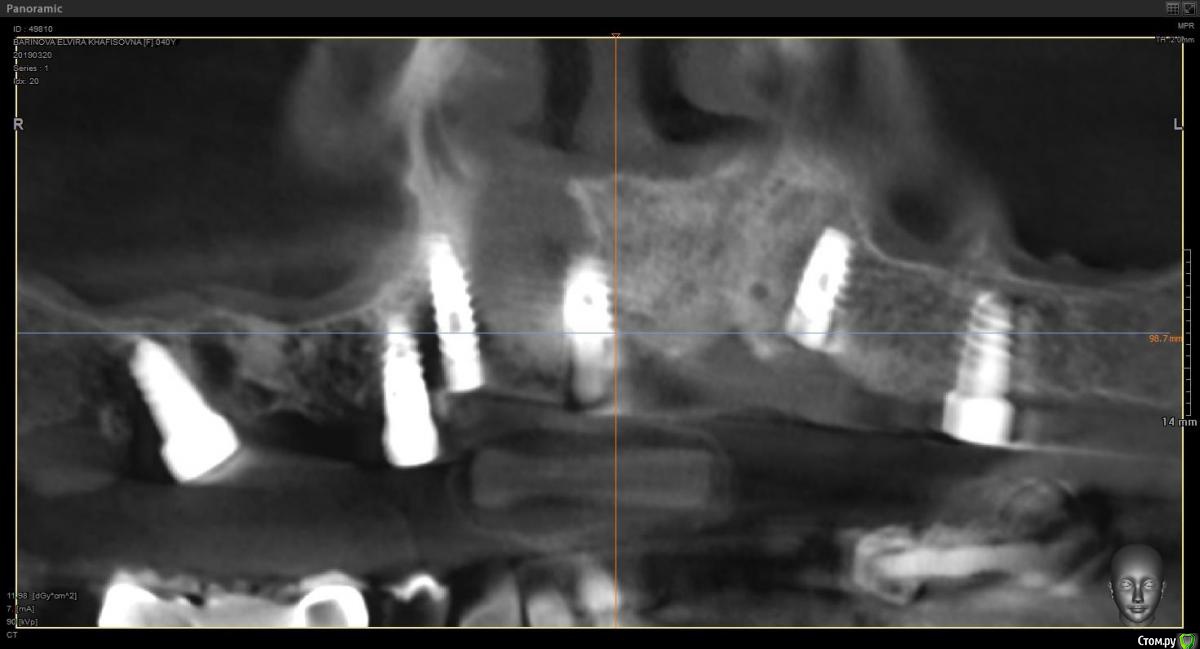

Витторио Орлионе Опубликовано 24 июня, 2019 Поделиться Опубликовано 24 июня, 2019 (изменено) Здравствуйте, уважаемые коллеги, позвольте обратиться за советом.Ситуация такова: 3 месяца назад были удалены все корни зубов на верхней челюсти, установлены 3 импланта MIS seven 1.4, 1.1, 2.6 с заглушками торк на момент установки составлял 35-40 Н/см, а взамен всех остальных нкр Biooss S, Biogide в связи с дегистенциями в области удаленных корней 1.6, 1.3, 2.4. Через 3 месяца планируется имплантация ещё 3 импланта с немедленной нагрузкой. А пока можно ли уже сейчас сделать временную конструкцию без вреда для костной пластики и какую? Изменено 24 июня, 2019 пользователем Витторио Орлионе Ссылка на комментарий

Витторио Орлионе Опубликовано 27 июня, 2019 Автор Поделиться Опубликовано 27 июня, 2019 А все сразу вместе с несъемными времяшками на имплантах побоялись делать?Насколько нужна временная конструкция пациенту если уже согласился 3 месяца ходитьтам была целая история, получилось так, что ещё три имланта в области 1.6, 1.3 и 2.4 сильно заглубил, после удаления были дегистенции вестибулярно, а мембан не было для их закрытия, в итоге эти импланты выкрутил и НКР, а пациентКА - родственница, жалуется на то что язык некуда деть, нижняя челюсть устаёт, жевать хочется, смеяться и улыбаться. Ссылка на комментарий